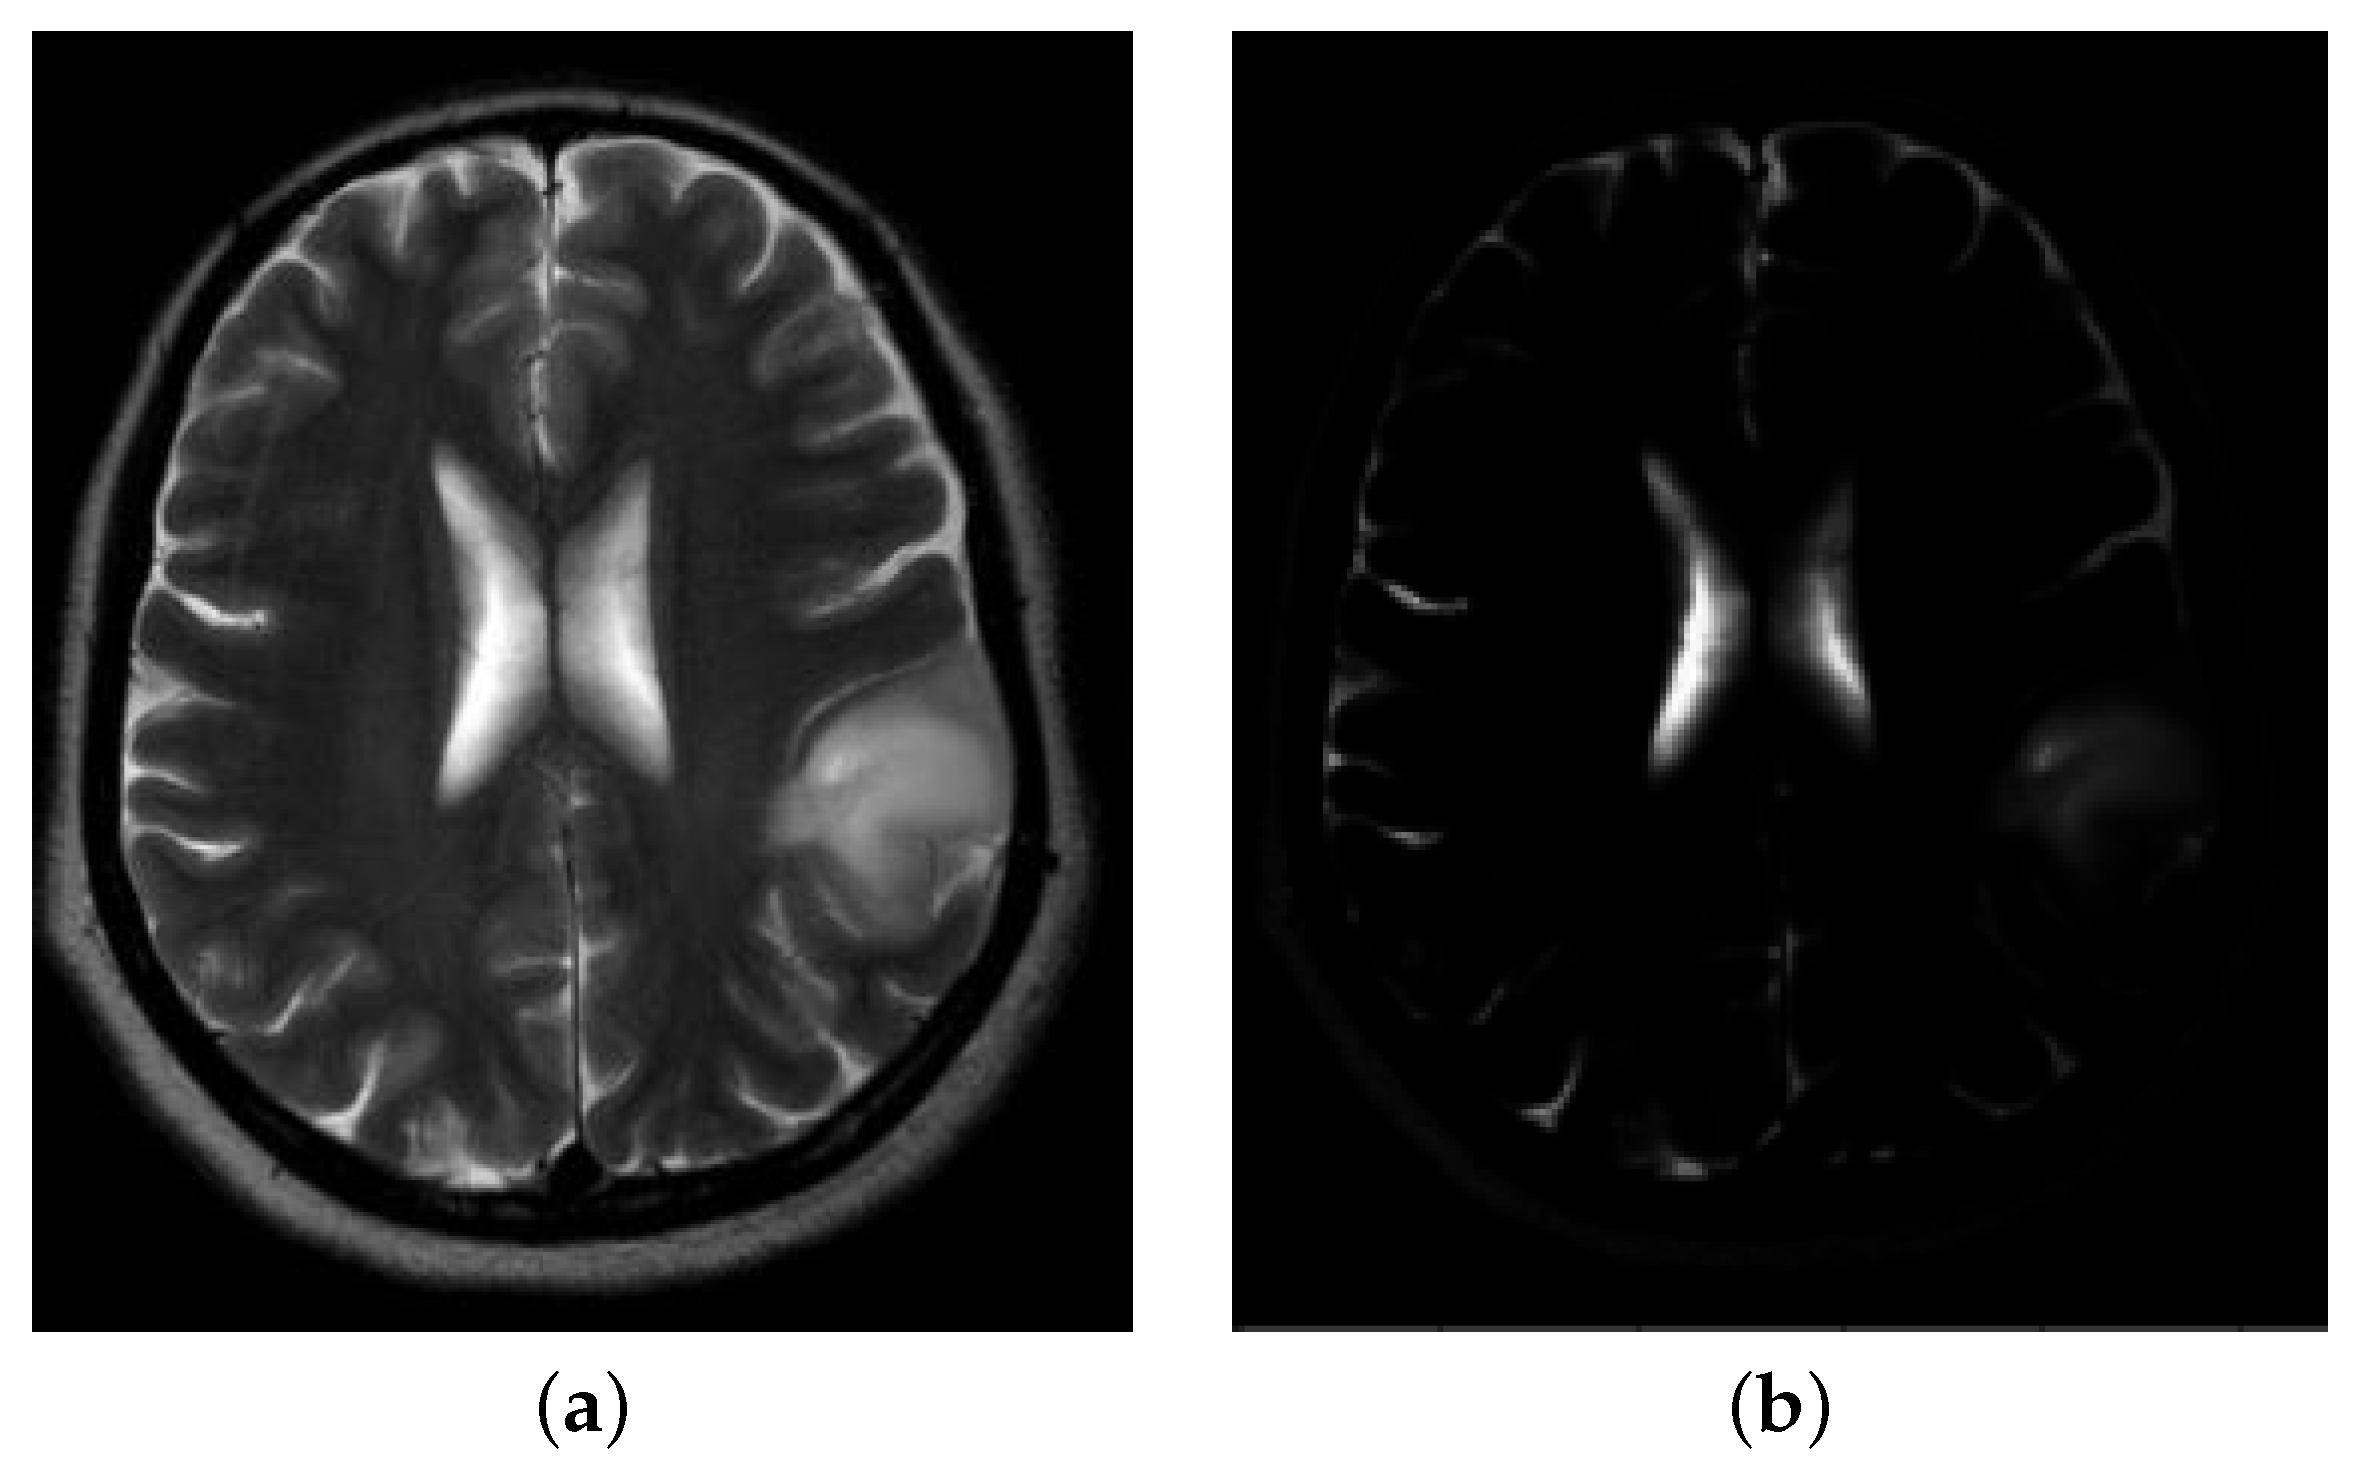

A Metastatic Brain Tumor Example

3.1. Pre-Processing